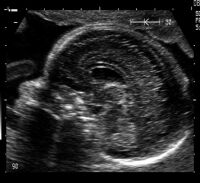

Başın iki temel ölçümü olan baş yatay çapı ve baş çevresi (BPD ve HC) alındıktan sonra öncelikle kafatası kemiklerinin bütünlüğü ve BPD kesitindeki doğal oval şekli görüntülendikten sonra kafa içi yapılar görüntülenir.

Normal kafa içi yapıların orta hatta birbirleriyle olan ilişkileri, beyin omurilik sıvısı üreten yapıların ve sıvıyı ileten kanalların özellikleri incelenir.

Daha sonra kafa içindeki yapılar insanda dengenin korunmasından sorumlu beyincik adı verilen organ seviyesine inerek incelenir. Burada beyincik dokusunun normal yapısal özellikleri incelendikten sonra beyinciğin hemen arkasında yeralan arka çukur adlı bölge gözden geçirilir. Buranın normal genişlikte olup olmadığı not edilir. Bu kesitte ense pilisi kalınlığı ölçümü de yapılır.

Bu resimde “gözlük” şeklindeki yapı beyincik dokusunu temsil ediyor.

Bu resimde beyincik dokusunun hemen solunda arka çukur gözleniyor.